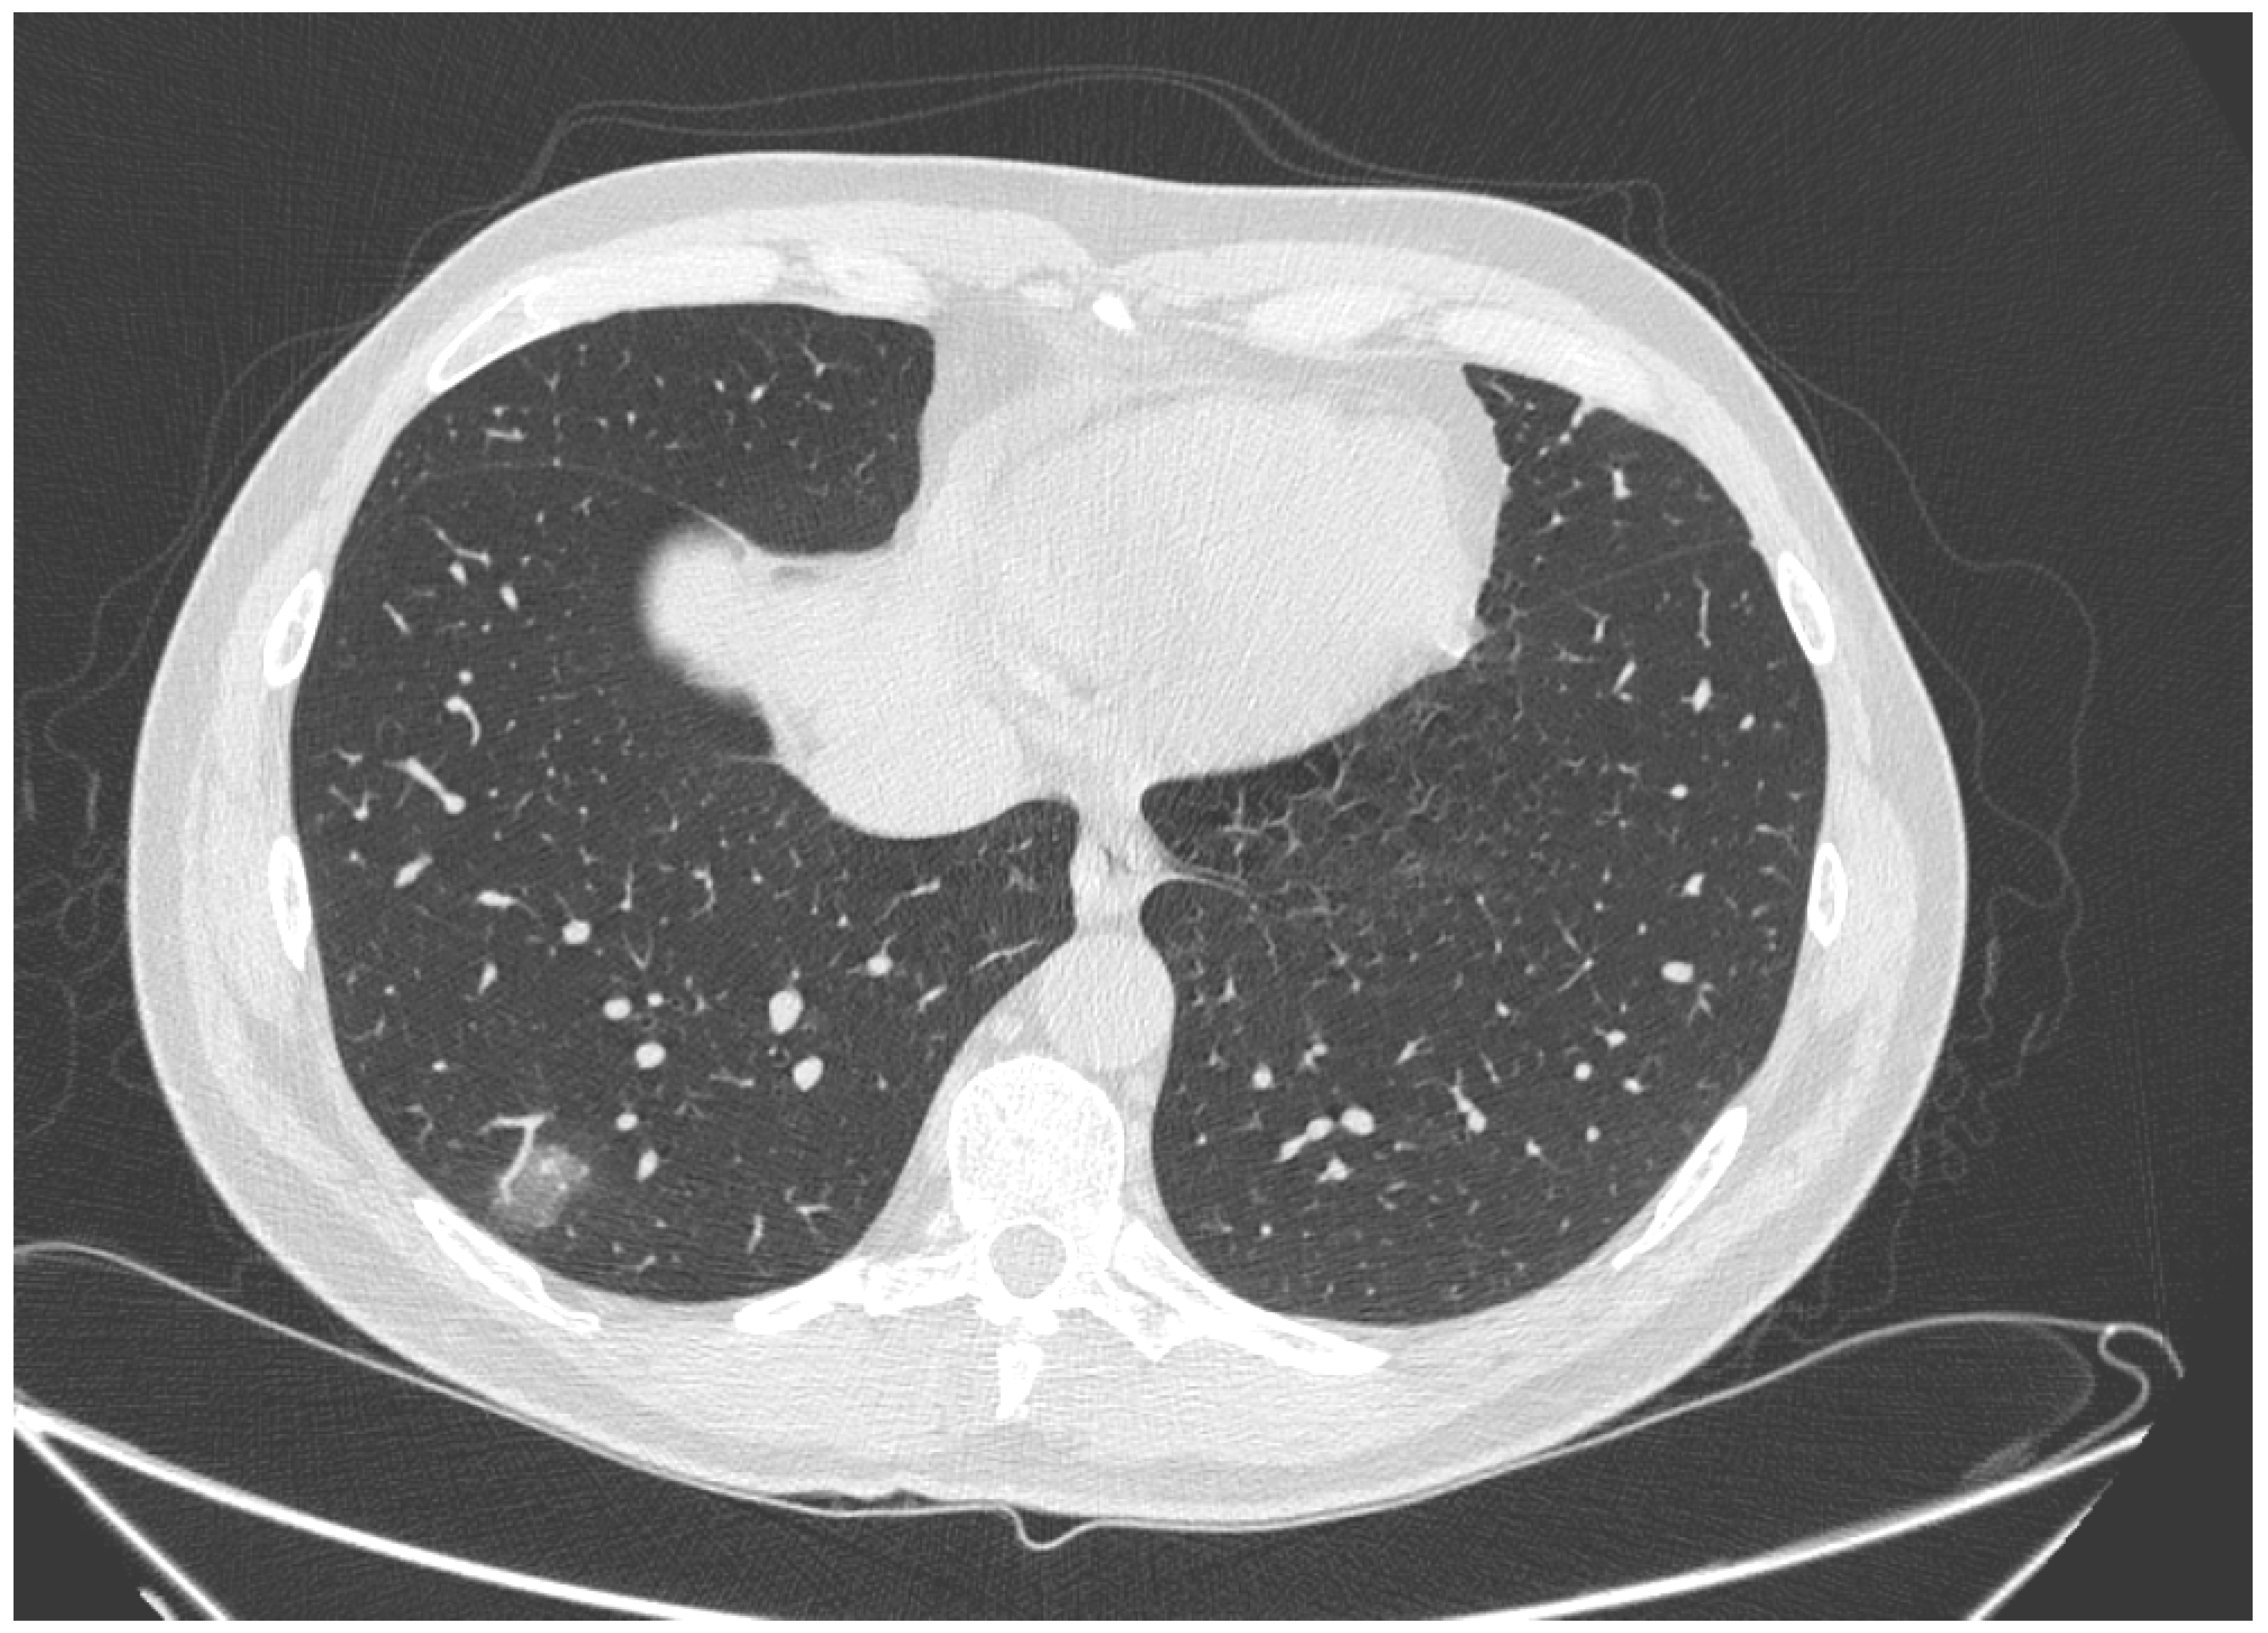

| High diagnostic confidence level | Bilateral multifocal GGO with predominantly peripheral distribution associated or not with septal thickening (crazy paving) and/or consolidations; multifocal GGO of rounded morphology associated or not with crazy paving and/or consolidations; multifocal GGO associated with findings of organizing pneumonia. |

| Intermediate diagnostic confidence level | GGO with diffuse distribution associated or not with crazy paving and/or consolidations; bilateral multifocal GGO and/or consolidations without a prevalent peripheral distribution and without rounded morphology; unilateral GGO with or without consolidation. |